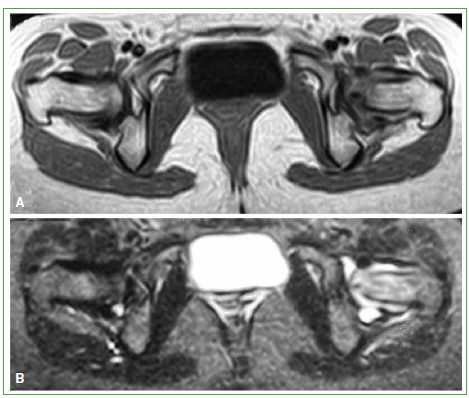

A los dos meses, se realiza una RM de caderas de control (28 de diciembre de 2019), corte coronal en secuencias potenciadas en T2 y T1. Se observa la persistencia del edema óseo en la cabeza y el cuello del fémur izquierdo y del derrame articular (Figura 4). En los cortes coronales en secuencias potenciadas en T1 y T2, se visualizan los mismos hallazgos (Figura 5).

Figura 4.

Resonancia magnética de caderas, corte coronal en secuencias potenciadas en T2 (A) y T1 (B). Se observa la persistencia del edema óseo en la cabeza y el cuello del fémur izquierdo, y también del derrame articular.

Figura 5.

Resonancia magnética de caderas, corte coronal en secuencias potenciadas en T1 (A) y T2 (B). Se observa la persistencia del edema óseo en la cabeza y el cuello del fémur izquierdo, y también del derrame articular.